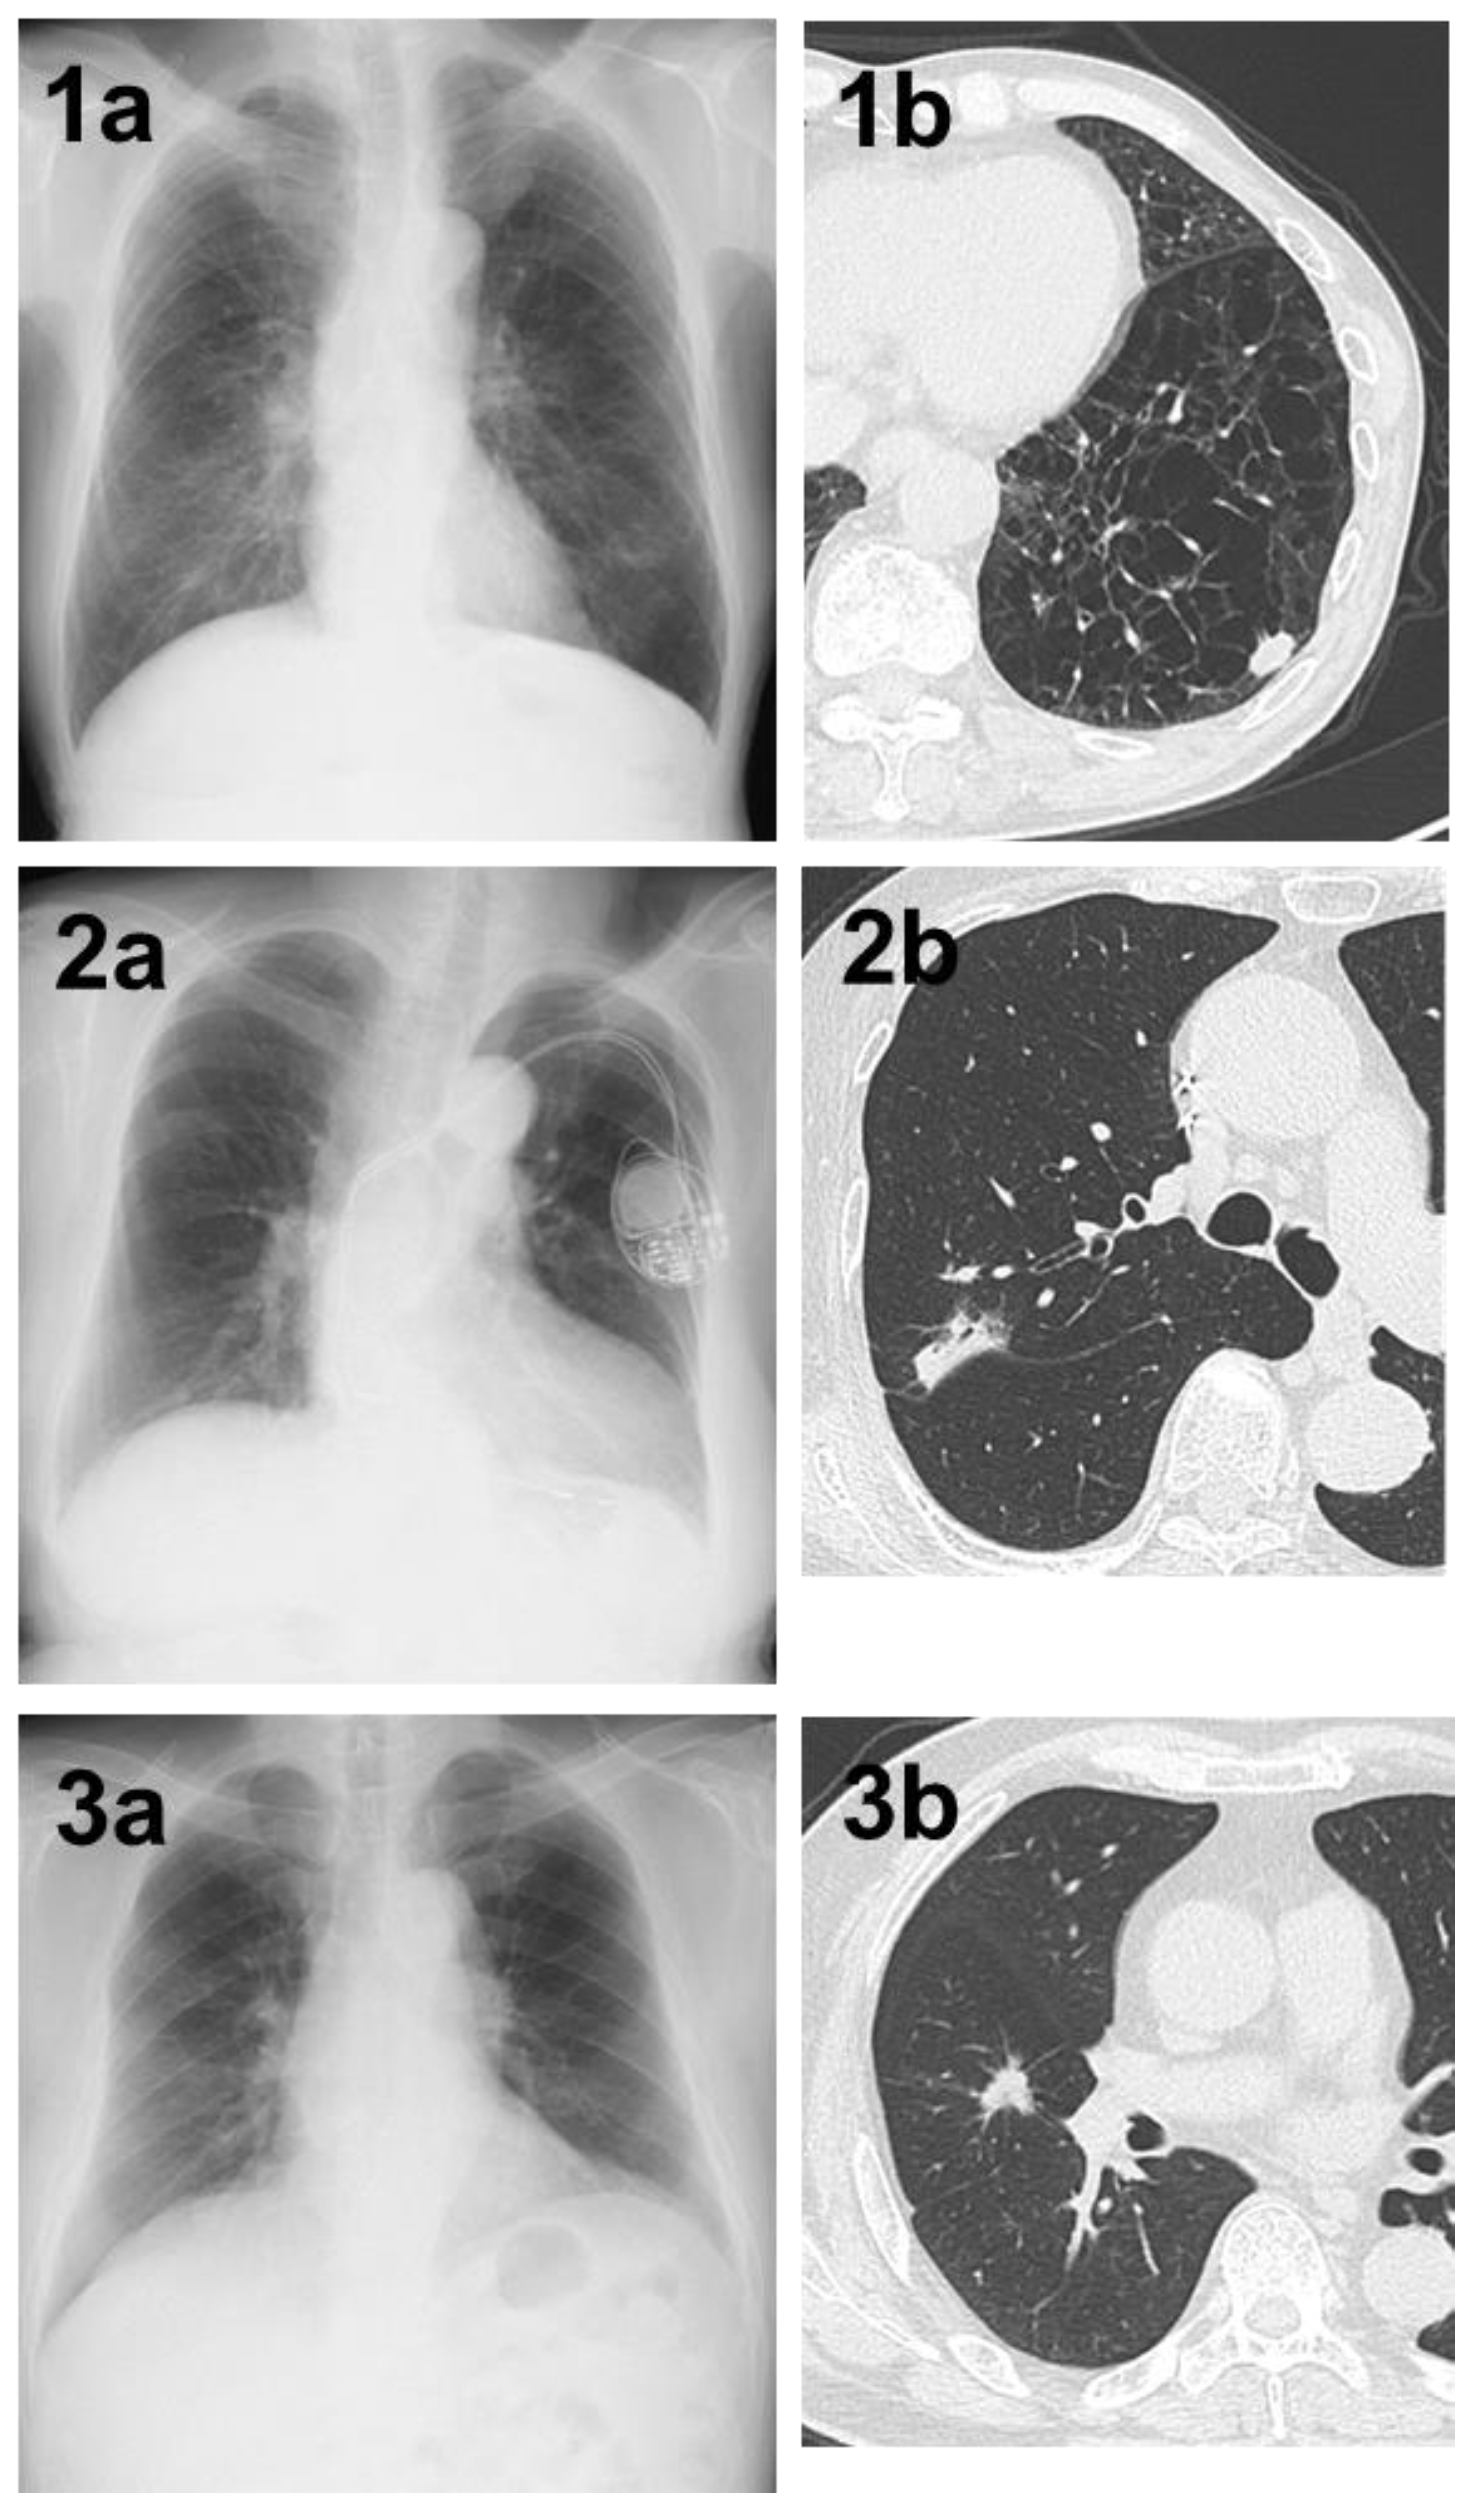

Figure 3. (1a) A shadow in the left lower lung field that was not determined by AI. (1b) Chest CT showing a nodule with a total and solid size of 1.5 cm in the left S⁹ region on the basis of strong emphysematous changes in the lung. The histopathological diagnosis was squamous cell carcinoma, total tumor and invasive size of 1.5 cm, pT1bN0M0 (stage IA2). (2a) A shadow in the right upper lung field that could not be determined by AI. (2b) Chest CT showing a nodule with a pleural indentation, total size of 2.8 cm, solid size of 2.3 cm, in the right S2 region. The histopathological diagnosis was adenocarcinoma (papillary adenocarcinoma), total tumor and invasive size of 3.4 cm, pT2aN0M0 (stage IB). (3a) A shadow in the right middle lung field that could not be determined by AI. (3b) Chest CT showing a nodule with a total and solid size of 1.5 cm in the right S⁴ region. The histopathological diagnosis was adenocarcinoma (acinar adenocarcinoma), total tumor size of 1.5 cm, invasive size of 1.4 cm, pT1aN0M0 (stage IA2).

The main reasons why lung tumors could not be detected by the AI in 84 cases are listed in Table 2. Thirty-five cases had lesions overlapping with anatomical structures, such as the mediastinum, heart, and clavicle, or lesions below the diaphragm. Eight of these 35 cases were detectable by physicians (Figure 1). Conversely, there was one case in which it was difficult for physicians to detect the shadow overlapping the anatomical structures, but it was detected by AI (Figure 2). Eighteen cases were AIS, thirteen were lepidic adenocarcinoma (invasive size: 0.05–2.0 cm), and six were small nodules less than 0.7 cm in diameter. The other six cases were difficult to visualize on chest radiographs. Of these six cases, three cases had ground-glass components as the main component on CT, and one case had nodule and pulmonary vessels visible in succession. Many of these lesions were difficult to visualize due to the imaging conditions. Six patients did not fit these conditions; their lesions could be determined by physician interpretation, and their non-detection was judged to be an oversight by the AI (Figure 3).